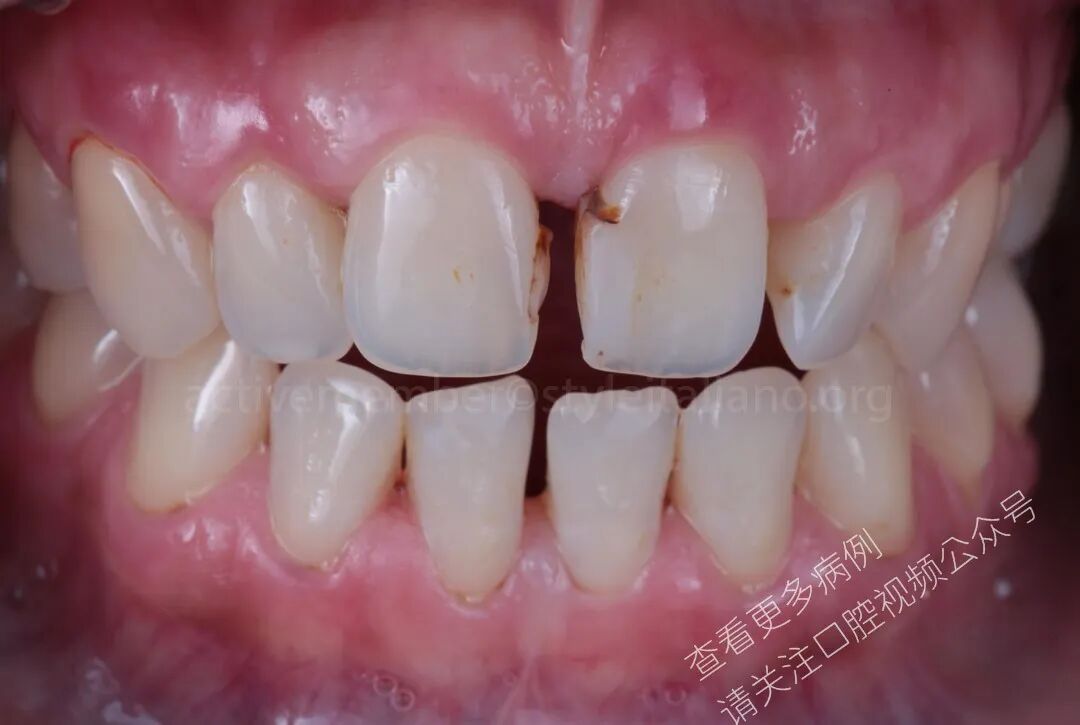

图1:口内照显示旧有复合树脂及龋坏患者就诊于本诊所,要求关闭上颌中切牙之间的牙间隙,以改善其笑容的美观性与协调性。

图3:可见微渗漏的旧有复合树脂除患者希望关闭上颌中切牙间隙外,临床检查还发现中切牙近中区域存在旧有复合树脂修复体伴继发龋。

图4:关闭牙间隙前的口内照在制定牙间隙关闭方案时,必须谨慎选择修复技术,以确保操作简便、快速且可预测,能够建立新的接触点、新的接触区以及自然且符合生物学原则的穿龈轮廓。同样重要的是评估前牙的比例与对称性,以确保最终修复体呈现自然、协调且美学平衡的笑容。